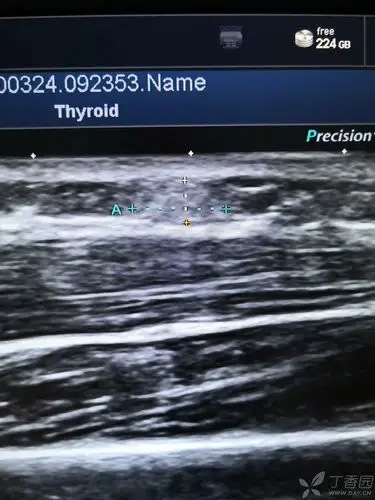

请问这个是脂肪瘤吗

小孩子两周,右小腿有个小隆起的包一样的,做完b超,医生说是脂肪瘤